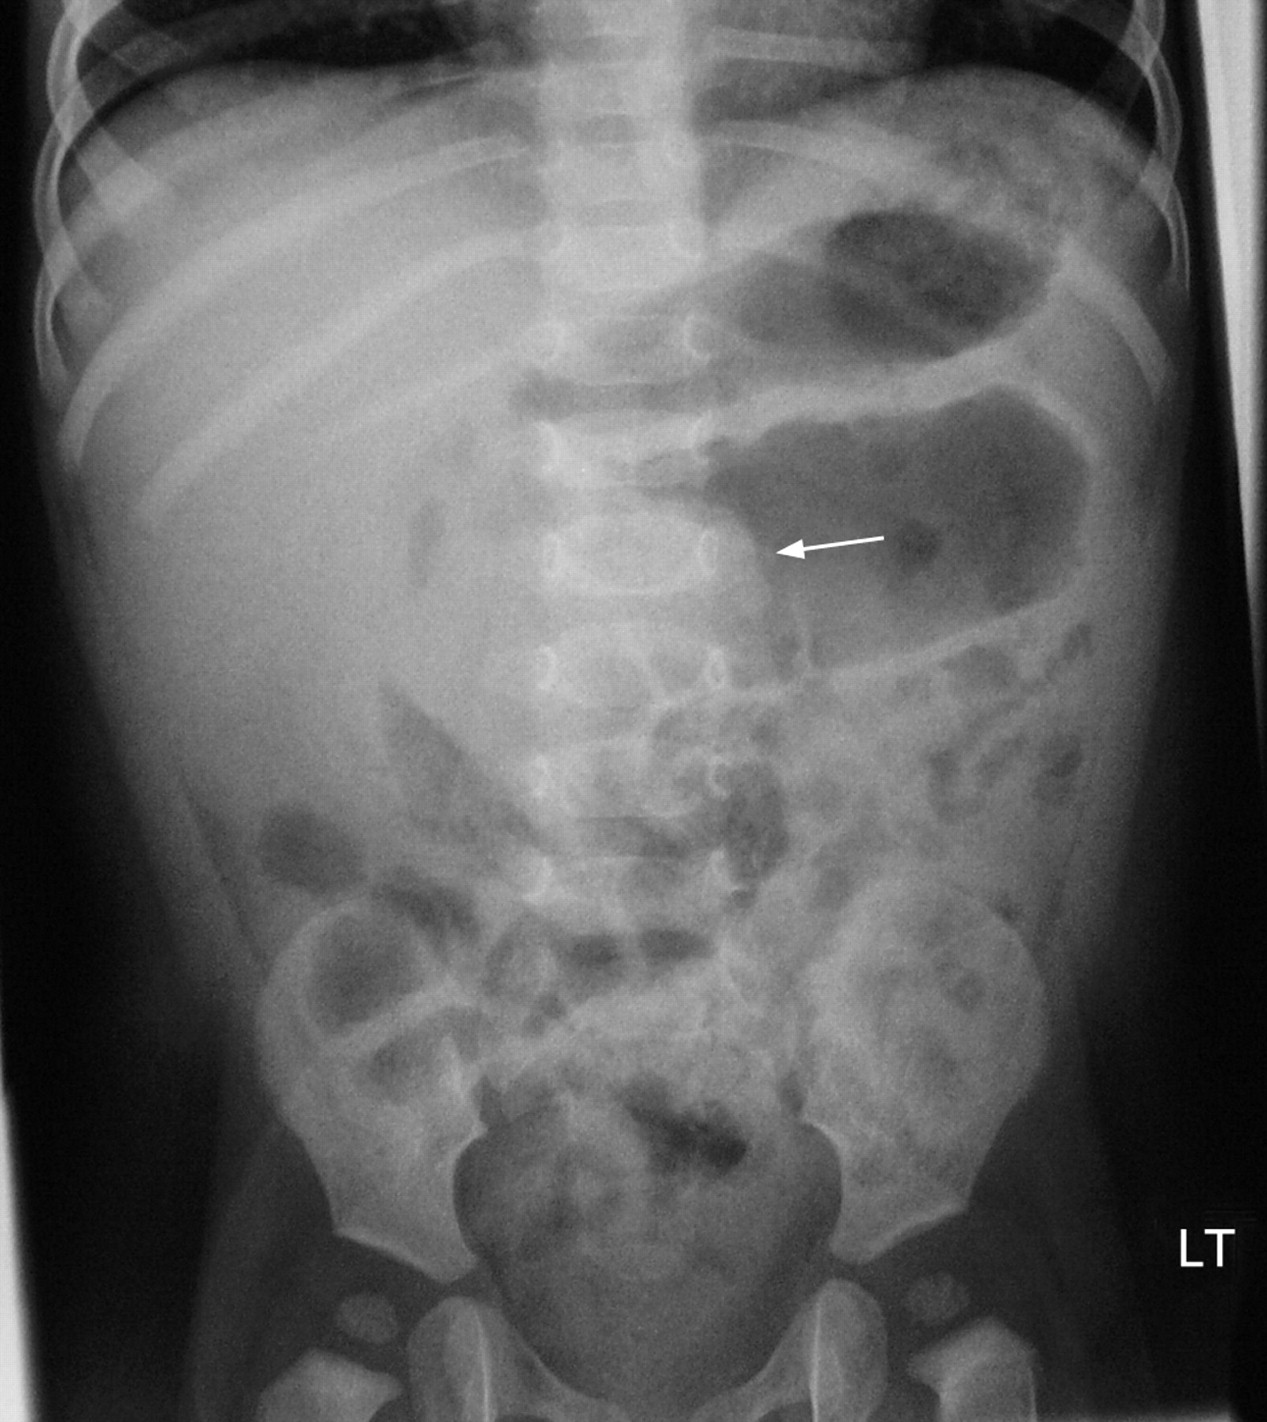

There may be an absence of gas in the distal collapsed bowel. Intussusception is caused by part of the intestine being pulled inward into itself. Intussusception often involves both small and large bowels. 1) target sign, 2) crescent sign, 3) absent liver edge sign (also called absence of the subhepatic angle), and 4) a bowel obstruction. Thus, intussusception should be.

[ 1, 2, 3] invagination of a bowel segment (usually, the small bowel) into the lumen of the. Symptoms include abdominal pain which may wax and wane, vomiting, bloating, and bloody stool. Plain abdominal xray of patient is done in supine and upright position. An abnormal gas pattern, with an empty right lower quadrant and visible soft tissue mass in.

Recall that the target sign is a mass in the right upper quadrant. Intussusception often involves both small and large bowels. Intussusception was confirmed on ultrasound. An intussusception is sometimes discovered incidentally during an imaging study performed for other reasons or for nonspecific symptoms. Intussusception is a condition in which part of the intestine folds into the section next to.

This telescoping action often blocks food or fluid from passing through. The pressure created by the walls of the intestine pressing together causes: Intussusception is a condition that causes part of the bowel to fold into itself like a telescope. In some babies, the intussusception fixes itself during a barium enema. To summarize, the radiographic signs of intussusception are:

Other complications may include peritonitis or bowel. This may occur due to the pressure on the intestine while barium is introduced into the intestines. An abnormal gas pattern, with an empty right lower quadrant and visible soft tissue mass in the upper abdomen a soft tissue mass surrounded by a crescent lucency of bowel gas (crescent sign) lack of faecal.